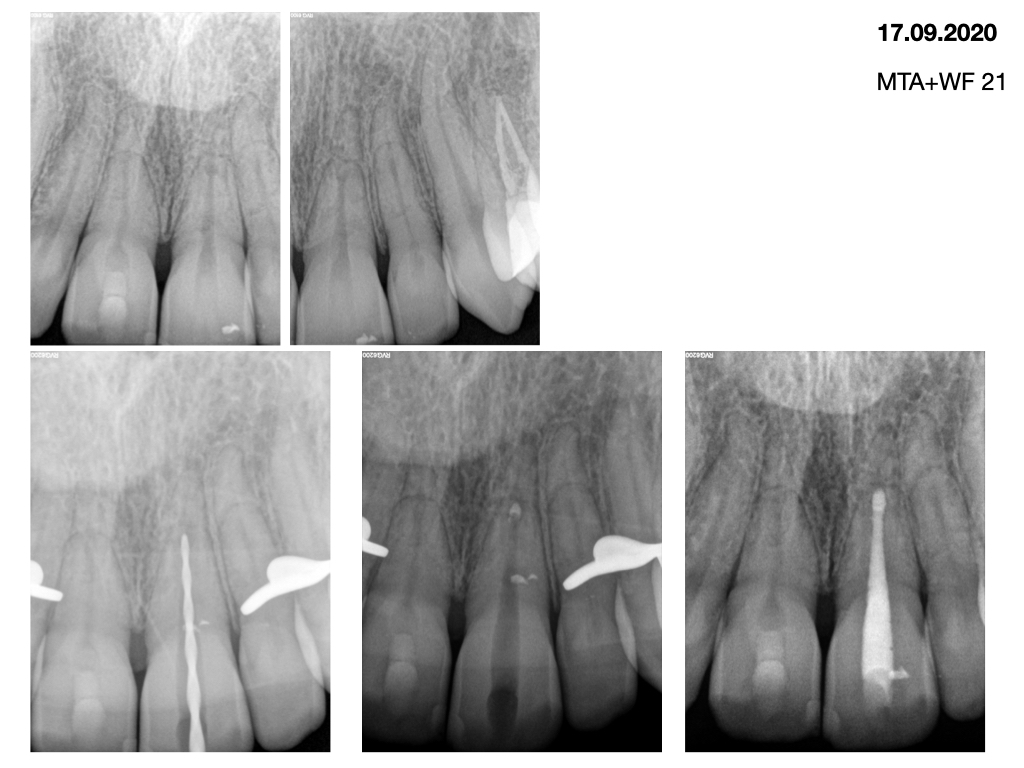

Wurzelfrakturen